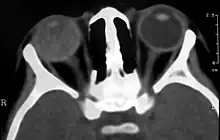

Imaging findings

Imaging studies such as ultrasonography (US), Computerized Tomography (CT) and Magnetic Resonance Imaging (MRI) can aid diagnosis. On ultrasound, Coats' disease appears as a hyperechoic mass in the posterior vitreous without posterior acoustic shadowing; vitreous and subretinal hemorrhage may often be observed.[7][8]

On CT, the globe appears hyperdense compared to normal vitreous due to the proteinaceous exudate, which may obliterate the vitreous space in advanced disease. The anterior margin of the subretinal exudate enhances with contrast. Since the retina is fixed posteriorly at the optic disc, this enhancement has a V-shaped configuration.[2]